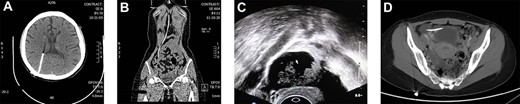

During the surgery, the patient was placed from Trendelenburg position to supine position because the patient’s forehead hemangioma was swelling sharply in Trendelenburg (Fig. 2a). The current procedure was performed using standard 4 port technique. The pneumoperitoneum was maintained at 10 mmHg. Throughout the operation, the end of the catheter was exposed, clear cerebrospinal fluid was dripped from the catheter continuously (Fig. 2b). After excising the right adnexa, rapid pathology revealed right ovary borderline mucinous cystadenoma. The patient was discharged on the third day after surgery. In the recent follow-up, 5-year after surgery, the patient was still in good condition with no complications or relapse.

(A) Swelling forehead hemangioma in Trendelenburg position; (B) The end of the catheter was exposed and clear cerebrospinal fluid was dripped from the catheter continuously.